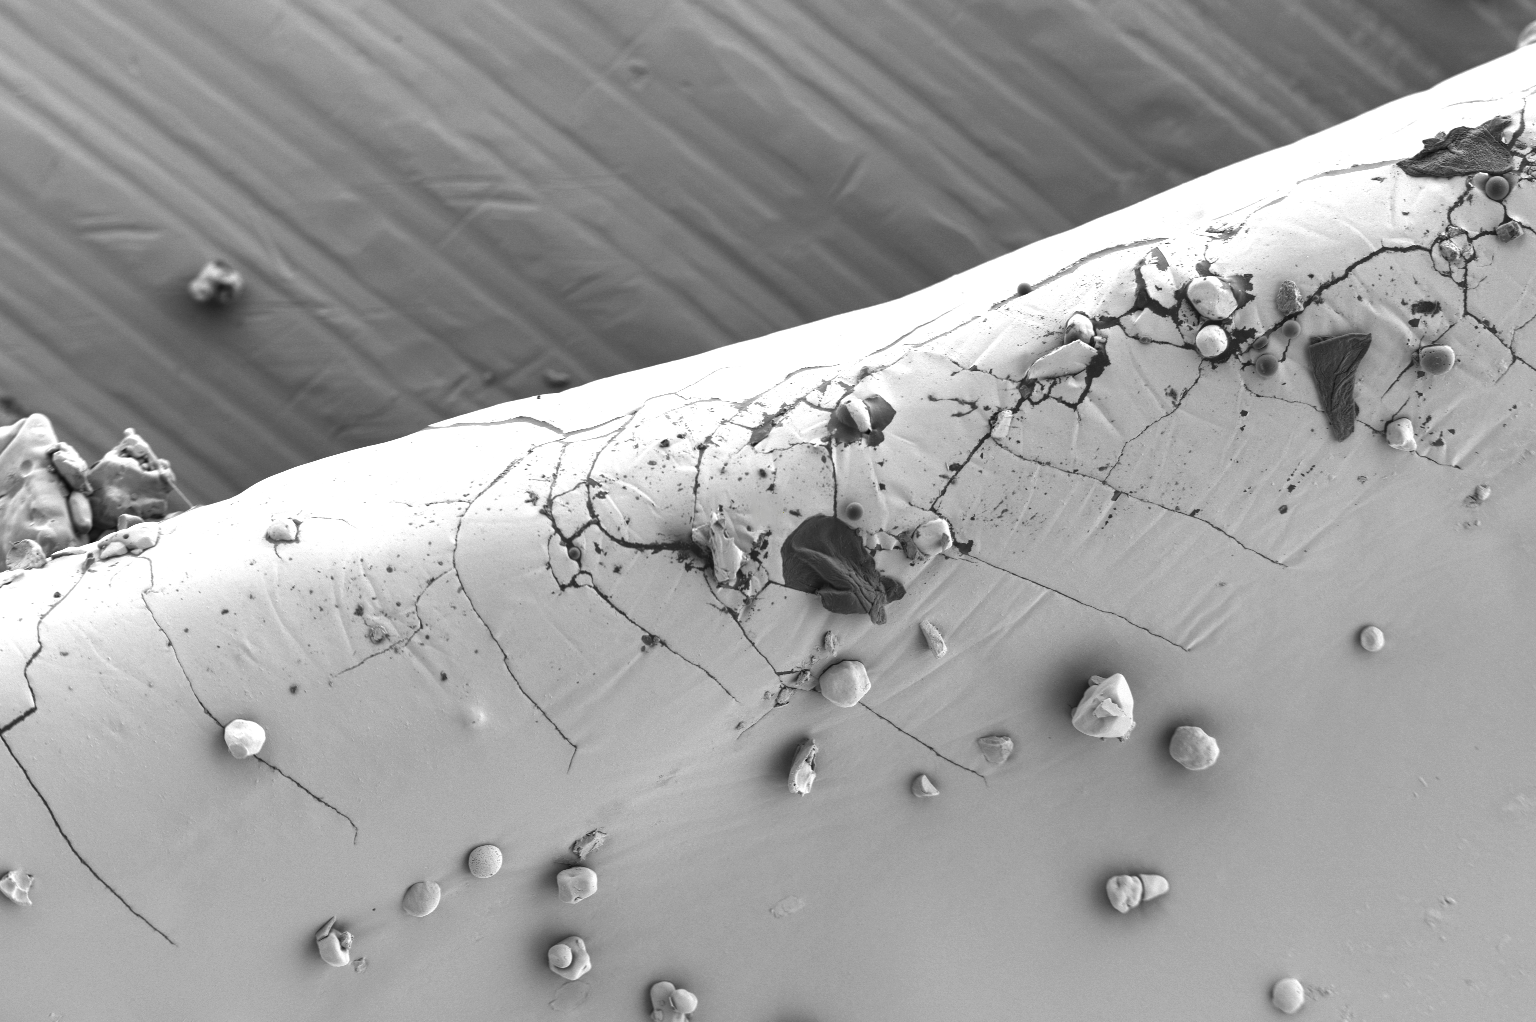

在异物与污染物鉴定方面,生产过程中可能引入的微小纤维、金属颗粒、聚合物碎屑等外来污染物,是药品品质控制中的重大风险点。扫描电镜的高分辨率成像能够精确定位并识别这些异物的物理形态,为污染源调查提供重要依据。比如,在对硫酸氨基葡萄糖胶囊壳进行常规质量审计时,光学显微镜下观察到表面存在微小的斑点和疑似裂纹。进一步通过扫描电镜的高倍率观察发现,胶囊壳原本光滑的表面存在明显的微观结构缺陷:表面可见明显的微裂纹,同时附着有若干不规则形状的片状杂质,见图1a。这些微裂纹呈现典型的应力腐蚀特征,可能与包衣过程中的干燥速率梯度和聚合物内应力释放有关。杂质与胶囊壳基质在形貌上存在显著差异(图1b为未被污染的胶囊壳基质),通过与典型微生物形貌特征比对,排除了微生物污染的可能性,推断其为生产环境或辅料中的无机粉尘污染。这一发现为企业改进包衣工艺参数、加强生产环境控制提供了直接的微观证据。

图1a 硫酸氨基葡萄糖胶囊壳表面可见明显不规则片状污染物和微裂纹,且污染物充填裂纹缝隙

图1b 未被污染的硫酸氨基葡萄糖胶囊壳基质